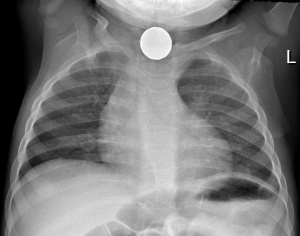

Aspirated foreign body

- CXR

- Useful to confirm diagnosis, does not rule out

- Negative in >50% of tracheal foreign bodies, 25% of bronchial foreign bodies[3], and may be missed if very small and/or radiopaque

- Inspiratory/expiratory films may show relative hyperinflation proximal to obstruction on end-expiration

- Consider lateral decubitus films on right and left side